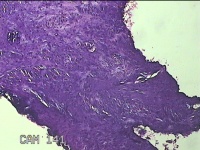

宫颈锥切物

性别

女

年龄

36岁

临床诊断

宫颈CIN2 宫颈乳头病毒感染

一般病史

检查发现CIN21个月。

标本名称

大体所见

灰白粉红色组织5.5x1.3x0.8cm一块,表面糜烂,切面灰白粉红色,质软,另有灰白粉红色组织2.3x2x0.3cm一堆,表面糜烂,切面灰白粉红色,质中。